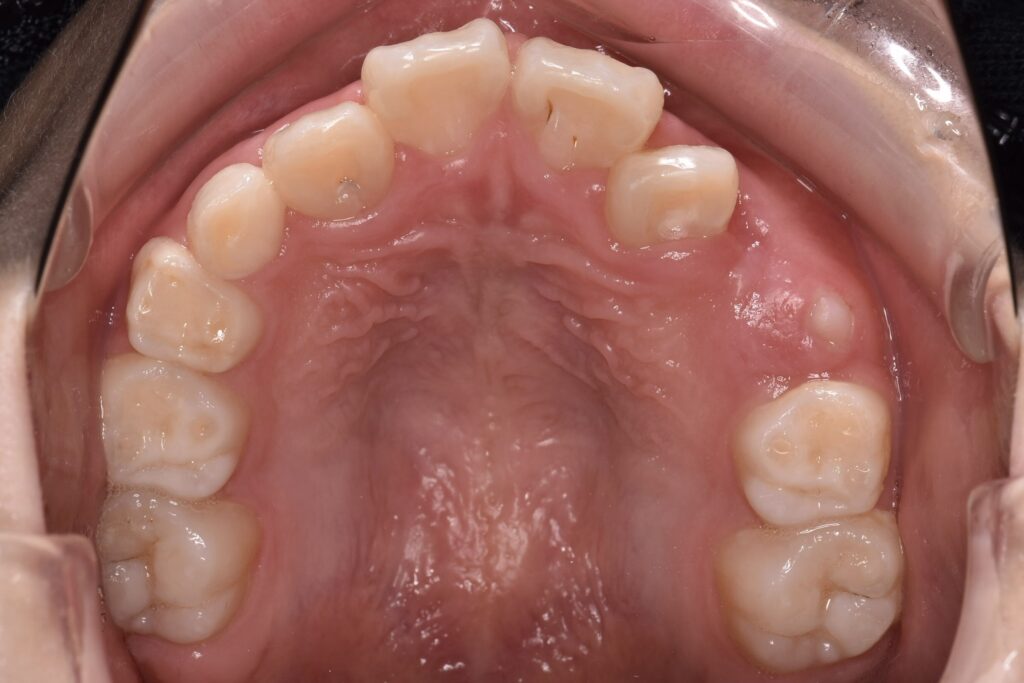

奥歯の咬む面(咬合面)は、山や谷が入り組んだ形をしていて、見た目以上に深い溝があります。

見た目はきれいに磨けているようでも、溝の奥には汚れが残りやすいのが現実です。